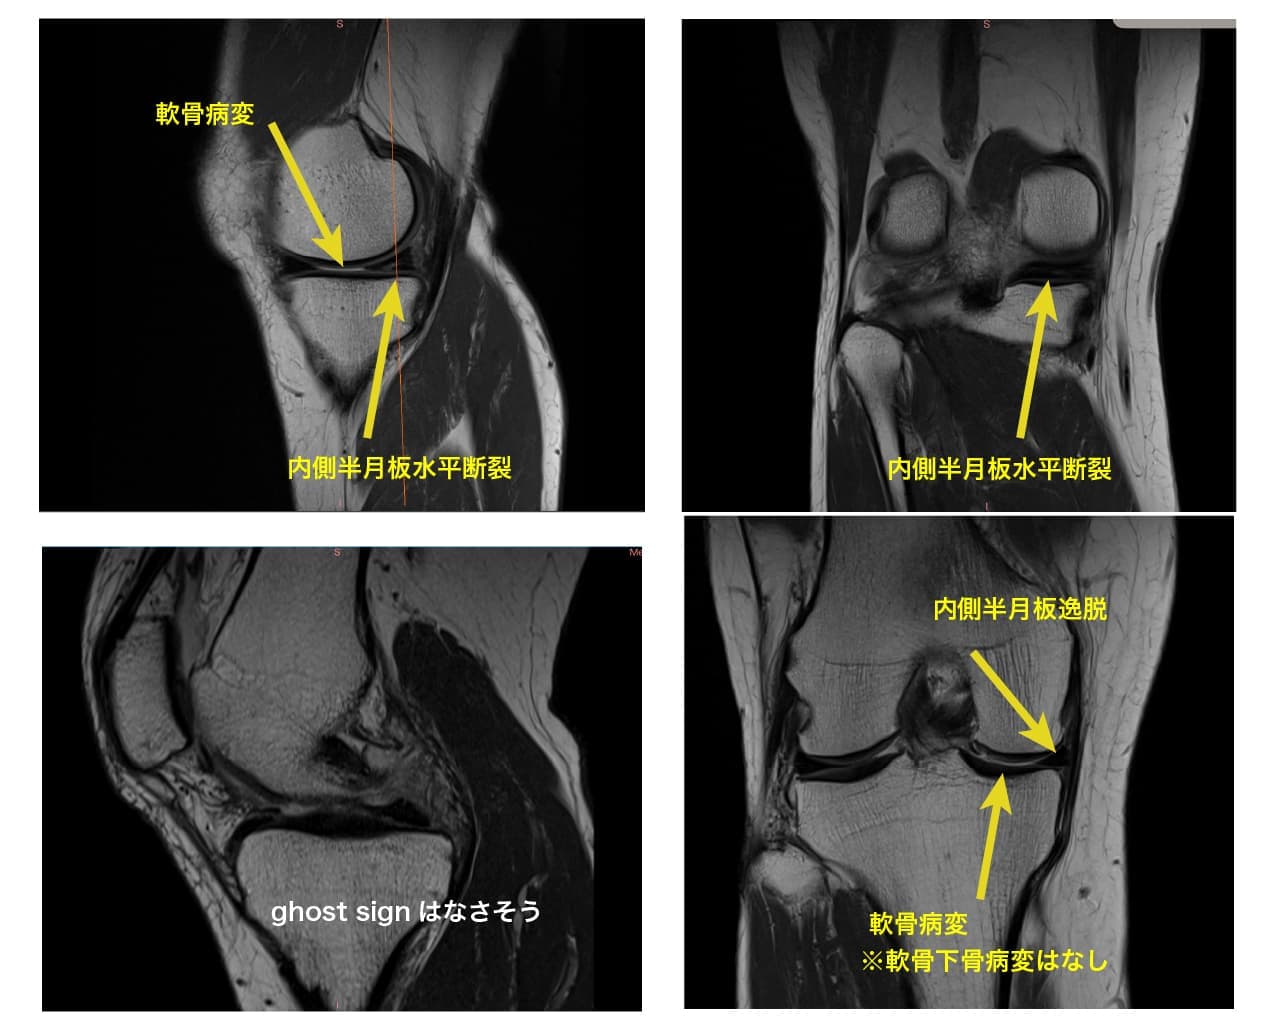

MRI画像を元にした診断と徒手療法

半月板には膝関節へ掛かる荷重ストレスを分散させるhoop機能というものがあります。

この機能が半月板損傷や逸脱によって破綻してしまうと、変形性膝関節症に発展していきます(急激な変形の進行の一因としてもhoop機能の破綻が関与していると言われています)。

その為、下のような画像が検査で判明したら、今のうちに出来る対応をしていく必要があります(MRIを提供してくれた患者様は、酷い変性は見当たらず経過観察となっていました)。

・荷重が偏らないように膝の使い方の再教育

・筋肉による膝関節の補強

・股関節や足関節といった関連部位の改善

など、様々な方法で状態を悪化させないようにしていきますが、『同じ症状』=『同じ問題』ではなく、リハビリの順序も一人一人違うため、その方にあった選択をしていく事が重要です。